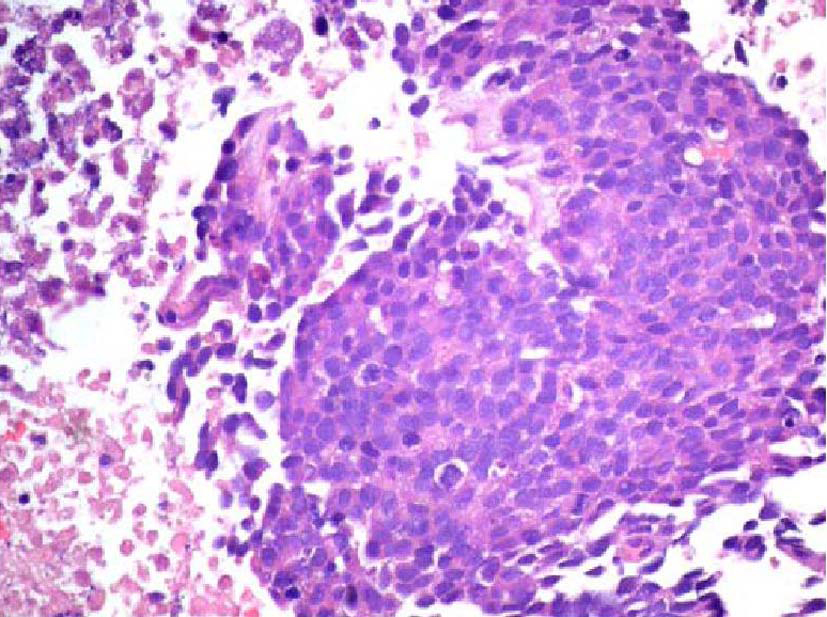

The patient was a 68-year-old Hispanic man who had a medical history of hepatitis B treated with lamivudin monotherapy, which was terminated in 2001. Periodic hepatic ultrasound follow-up showed a mass on the left lobe of the liver. A CT scan of the abdomen revealed a 4.0 cm mass located in the hepatic segment IV (Fig. 1). The serum level of alpha-fetoprotein (AFP) at this time was 1,191 ng/ml. The patient had normal liver enzymes and total bilirubin of 0.4 mg/dl. CA19-9 and CA125 were normal. CT of chest and extrahepatic abdomen showed no other lesions. At our institution, a liver core biopsy was performed, which showed an extensively necrotic, epithelial malignant neoplasm (Fig. 2). An intraoperative ultrasound showed that the mass was located in segment IV extending to segment V for which an extended left hepatectomy was performed. Intraoperatively, the abdominal cavity, including omentum, peritoneum, intestines, stomach, and pancreas, were free of lesions. The specimen showed both a hepatocellular carcinoma and a neuroendocrine carcinoma (Fig. 3), confirmed by immunohistochemistry exam (Fig. 4). The patient was treated with four courses of chemotherapy regimen including Etoposide: 120 mg/m2 day 1 to day 3 and cisplatin: 80 mg/m2 day 2; the cycle was repeated every three weeks. The patient is free of recurrence with a follow-up of 28 months.

![]() Click for large image | Figure 2. Initial liver biopsy showing a necrotic poorly differentiated carcinoma (hematoxylin and eosin, × 200). |